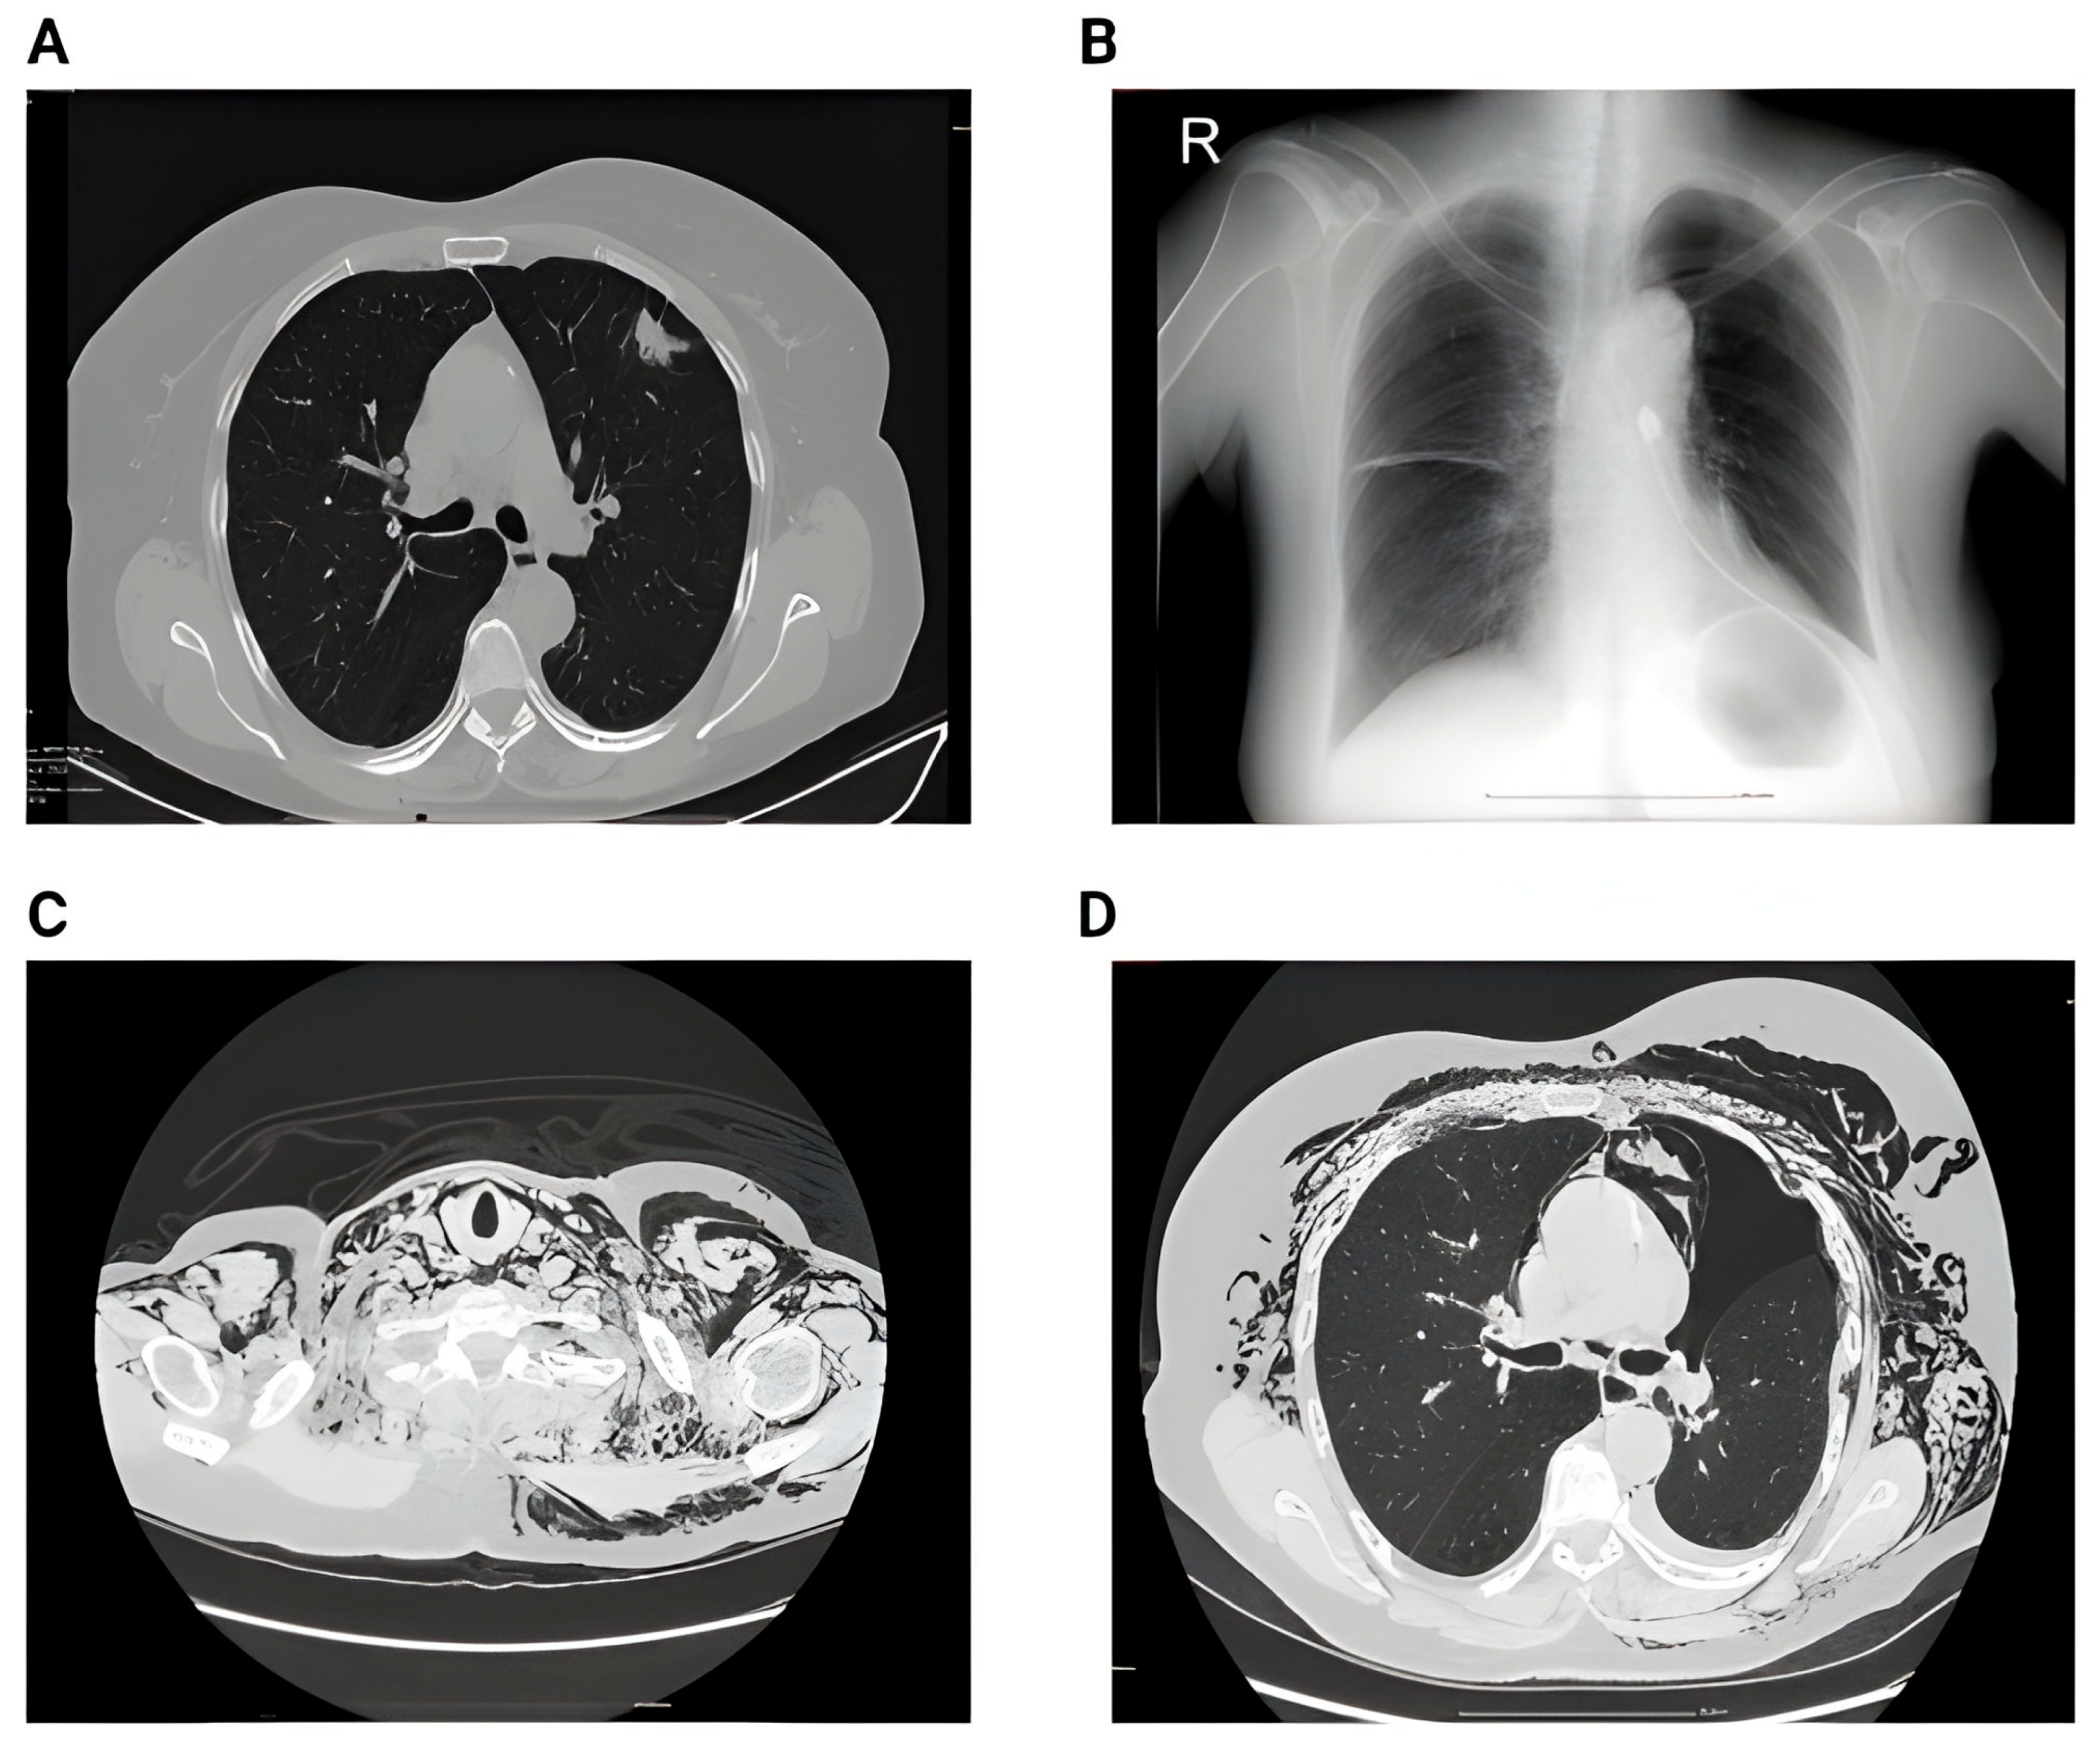

Representative imaging examples are provided in Figure 5 to illustrate the spectrum of radiological changes observed before and after lobectomy.

Figure 6 presents additional representative imaging findings that illustrate the postoperative spectrum following lobectomy.

Figure 5. (A) Preoperative image showing a large nodule in the middle lobe. (B) 2nd day postoperative x-ray showing small right pleural effusion, right basal infiltrates and bilateral basal atelectasis. (C) CT acquisition immediately after showing right pleural effusion, perihilar consolidation and ground-glass opacities, passive atelectasis. (D) One month postoperative showing full resolution of the postoperative complications after conservative therapy—no reintervention.

Figure 6. (A) Preoperative CT showing singular nodule in the left upper lobe with peri-nodular fibrosis. (B) 2nd day postoperative showing left pneumothorax and small subcutaneous emphysema. (C) 6th day postoperative showing impressive subcutaneous emphysema. (D) 6th day postoperative showing pneumothorax, subcutaneous emphysema and pneumomediastinum.